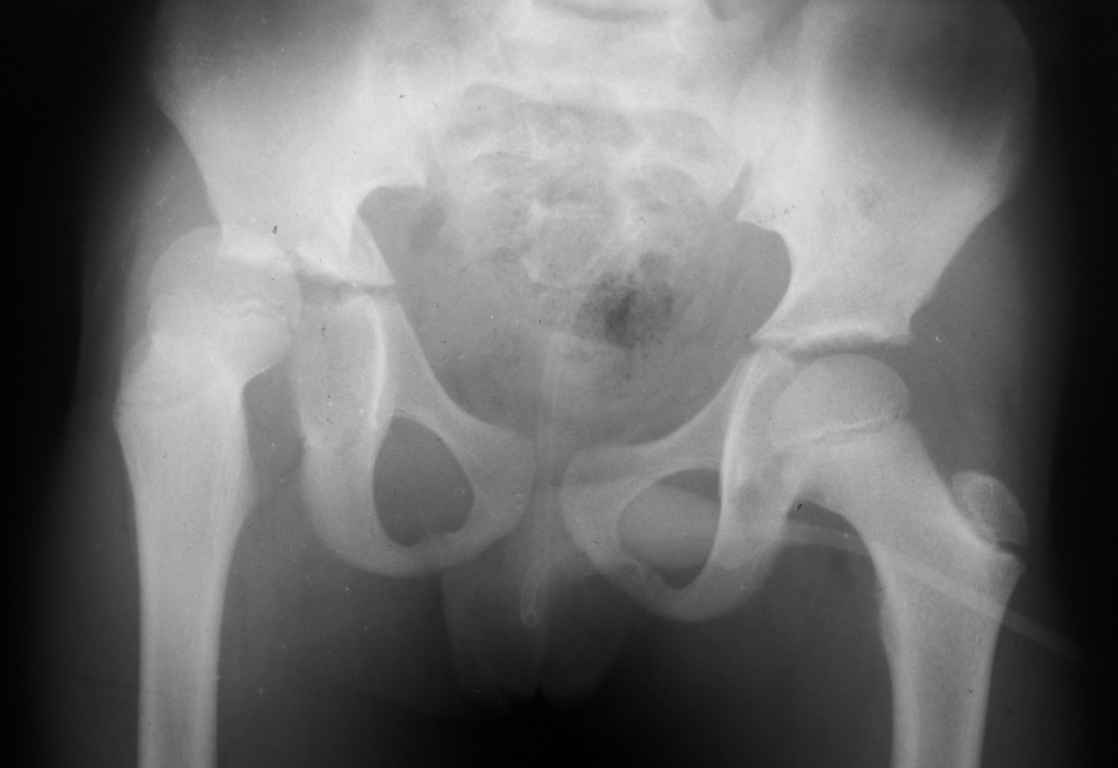

Уважаемые коллеги, помогите определиться с тактикой лечения.Ребёнок 7 лет, травма 11.09.08, поступил с травматическим вывихом бедренной кости.

Вывих вправлен, конечность фиксирована на скелетном вытяжении. Что делать с переломом подвздошной кости? Лечить консерватино или оперировать?